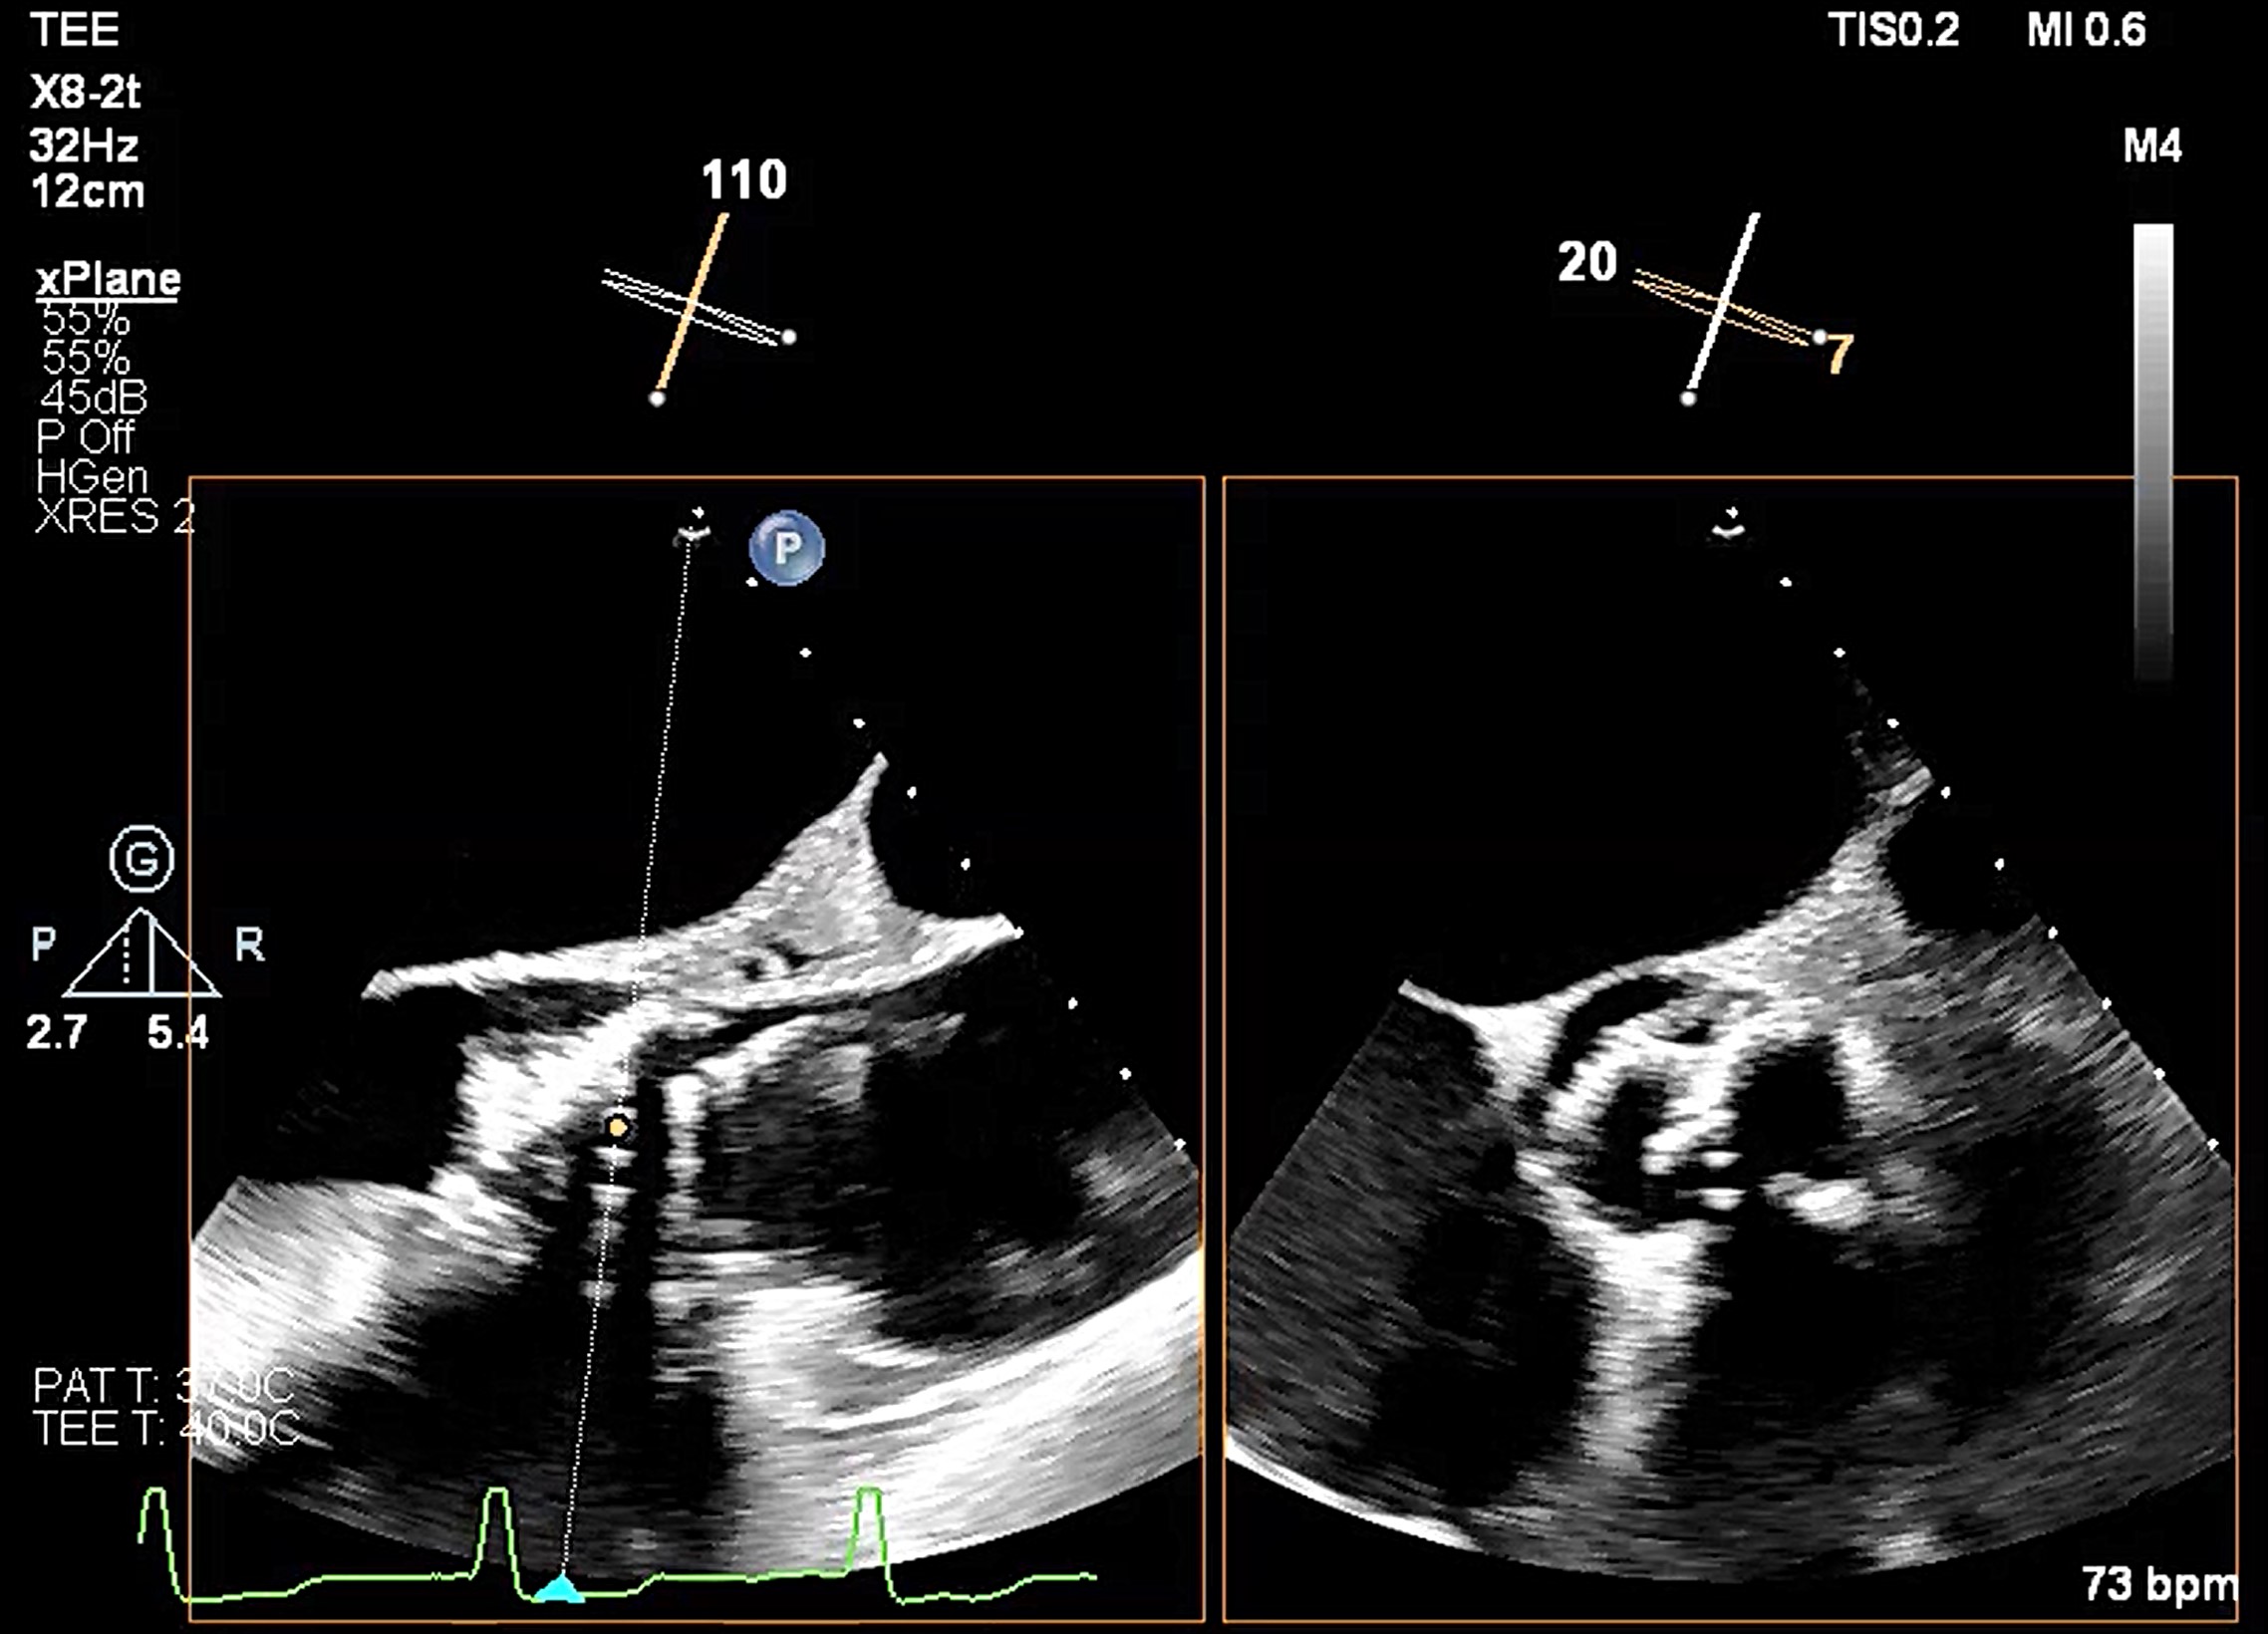

Transesophageal echocardiography revealed severe aortic regurgitation due to THV leaflet perforation following untreated infective endocarditis, along with a preexisting paravalvular leak caused by the calcified raphe of the type 1 bicuspid aortic valve.Given the patient’s deteriorating clinical status despite inotropic support, and after three negative blood cultures and five weeks of antibiotic treatment, the heart team decided to proceed with transcatheter treatment.

A combined procedure including transcatheter closure of paravalvular leak and redo-TAVR, was performed under general anesthesia with transesophageal echocardiographic guidance.1. Bilateral approach via left femoral artery(8Fr non-kinking sheath), right femoral artery(16Fr E-sheath).2. We used a Terumo guide wire accompanied with AL/5F diagnostic catheter to cross the defect of paravalvular leak.3. MP/7F guide catheter accompanied with 6 x 40mm Mustang balloon crossed the paravalvular leak defect by using balloon assisted tracking technique.4. Wire exchanged to Confida super-stiff wire.5. Amplatzer Vascular Plug II 9-12mm occluder was deployed successfully under TEE guidance. 6. TEE showed paravalvular leak downgrade to mild. There was no nearby structure damage, no new pericardial effusion, nor coronary obstruction.7. An Extra-small Safari super-stiff wire was placed in the left ventricle.8. A 23mm Sapien 3 valve was deployed successfully with 1cc overfill.9. The paravalvular leak and valvular AR both sealed successfully, with only minimal paravalvular leak remain.10. The transvalvular mean pressure gradient was 9mmHg, and the valve functioned well.